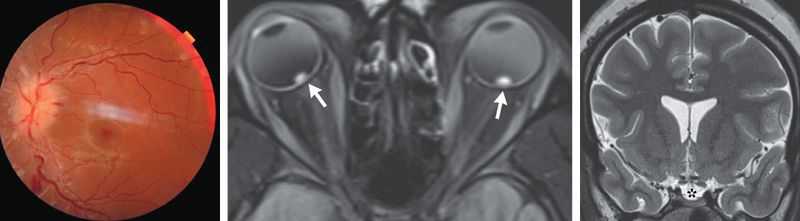

A 25-year-old woman with severe obesity presented to the emergency department with a 1-week history of blurred vision, headaches, and transient visual obscurations. Neurologic examination showed optic disk swelling and retinal hemorrhages in both eyes. An MRI and MRV of the head showed flattened posterior globes, an empty sella, and stenoses of the transverse sinuses without obstruction or thromboses. Which abnormality would most likely be notable from a lumbar puncture? Options A.Elevated opening pressure B.Elevated white blood cell count C.Oligoclonal bands D.Positive anti-aquaporin 4 antibody E.Xanthochromia